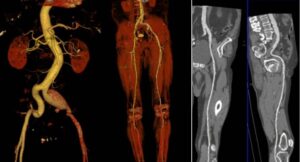

ΔΙΑΓΝΩΣΤΙΚΕΣ ΕΞΕΤΑΣΕΙΣ Κοιλιακής Αορτής και σπλαχνικών αρτηριών

Οι διαγνωστικές εξετάσεις για την αξιολόγηση της κοιλιακής αορτής και των σπλαχνικών αρτηριών μπορεί να περιλαμβάνουν τις εξής μεθόδους:

Οι διαγνωστικές εξετάσεις για την αξιολόγηση της κοιλιακής αορτής και των σπλαχνικών αρτηριών μπορεί να περιλαμβάνουν τις εξής μεθόδους:

- Αγγειογραφία της Κοιλιακής Αορτής και των Σπλαχνικών Αρτηριών (Celiac Artery Angiography): Αυτή η εξέταση χρησιμοποιείται για να αξιολογήσει την κατάσταση της κοιλιακής αορτής και των αρτηριών που εξυπηρετούν τα σπλάχνα. Συνήθως, περιλαμβάνει τη χρήση χρωματιστικού υγρού για εμφανή οπτικοποίηση των αγγείων στις ακτινογραφίες.

- Σπιράλ Υπολογιστική Τομογραφία (CT Angiography - CTA): Η CTA είναι μια μέθοδος εικονογράφησης που χρησιμοποιεί την τεχνολογία της υπολογιστικής τομογραφίας για τη δημιουργία λεπτομερών εικόνων των αγγείων. Συνήθως, περιλαμβάνει και τη χρήση χρωματιστικού υγρού για καλύτερη οπτικοποίηση των αγγείων.

- Μαγνητική Αξονική Τομογραφία (Magnetic Resonance Angiography - MRA): Η MRA είναι μια μέθοδος που χρησιμοποιεί το μαγνητικό πεδίο για τη δημιουργία εικόνων των αγγείων. Συνήθως, δεν απαιτεί τη χρήση χρωματιστικού υγρού.

- Δοπλερογραφία των Σπλαχνικών Αρτηριών (Doppler Ultrasound of Splanchnic Arteries): Η δοπλερογραφία χρησιμοποιείται για τον έλεγχο της ροής του αίματος στις σπλαχνικές αρτηρίες και την ανίχνευση πιθανών προβλημάτων, όπως στενώσεις ή ανευρύσματα.

Ο ιατρός θα επιλέξει την κατάλληλη μέθοδο ανάλογα με τα συμπτώματα, την ιατρική ιστορία και τις ανάγκες του ασθενούς.

Η Αξονική Αγγειογραφία (CTA) είναι μια ιατρική εξέταση που χρησιμοποιεί τεχνολογία της υπολογιστικής τομογραφίας (CT) για να παράγει λεπτομερείς εικόνες των αγγείων. Η CTA είναι ένα αποτελεσματικό μέσο για την αξιολόγηση του αγγειακού συστήματος και χρησιμοποιείται συχνά για την εξέταση των αγγείων σε διάφορα μέρη του σώματος.

Η Αξονική Αγγειογραφία (CTA) είναι μια ιατρική εξέταση που χρησιμοποιεί τεχνολογία της υπολογιστικής τομογραφίας (CT) για να παράγει λεπτομερείς εικόνες των αγγείων. Η CTA είναι ένα αποτελεσματικό μέσο για την αξιολόγηση του αγγειακού συστήματος και χρησιμοποιείται συχνά για την εξέταση των αγγείων σε διάφορα μέρη του σώματος.